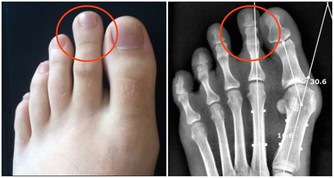

研究人員找到了110多位老人,在測試開始時和兩年後,分別掃描了他們的眼睛。他們發現,視網膜上硬疣形成物或黃斑的數量變化,與人的癡呆階段有關。在周邊視網膜中,堅硬的脈絡膜小疣的沉積,與阿爾茨海默病狀態顯著相關。

在對仍然符合標準的患者進行為期兩年的隨訪檢查後,研究者發現,在這些阿爾茨海默病患眼中,出現了更多玻璃膜疣沉積的區域。而且他們還觀察到,所有阿爾茨海默病患者的玻璃疣數量都在持續增加。

總的來說,參加研究的阿爾茨海默病患者中,有25%的人視網膜上有黃斑,相比之下,未患此病的患者只有4%有黃斑。